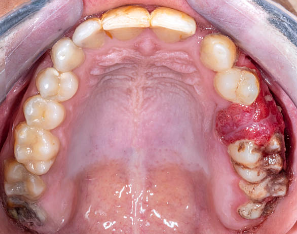

구강암은 입 안 점막, 혀, 잇몸, 입천장, 구강저(혀 밑부분) 등에서 발생하는 악성 종양을 말해요. 가장 흔한 형태는 편평 세포암으로, 전체 구강암의 대부분을 차지합니다.

✨ 구강암의 증상

구강암은 초기에 알아차리기 쉽지 않아요. 하지만 아래와 같은 증상이 있으면 꼭 확인해봐야 해요.

- 입 안에 치료해도 낫지 않는 궤양(상처)

- 붉거나 흰 반점이 오래 지속됨

- 씹을 때 통증이나 이물감

- 혀 또는 잇몸 부위 덩어리